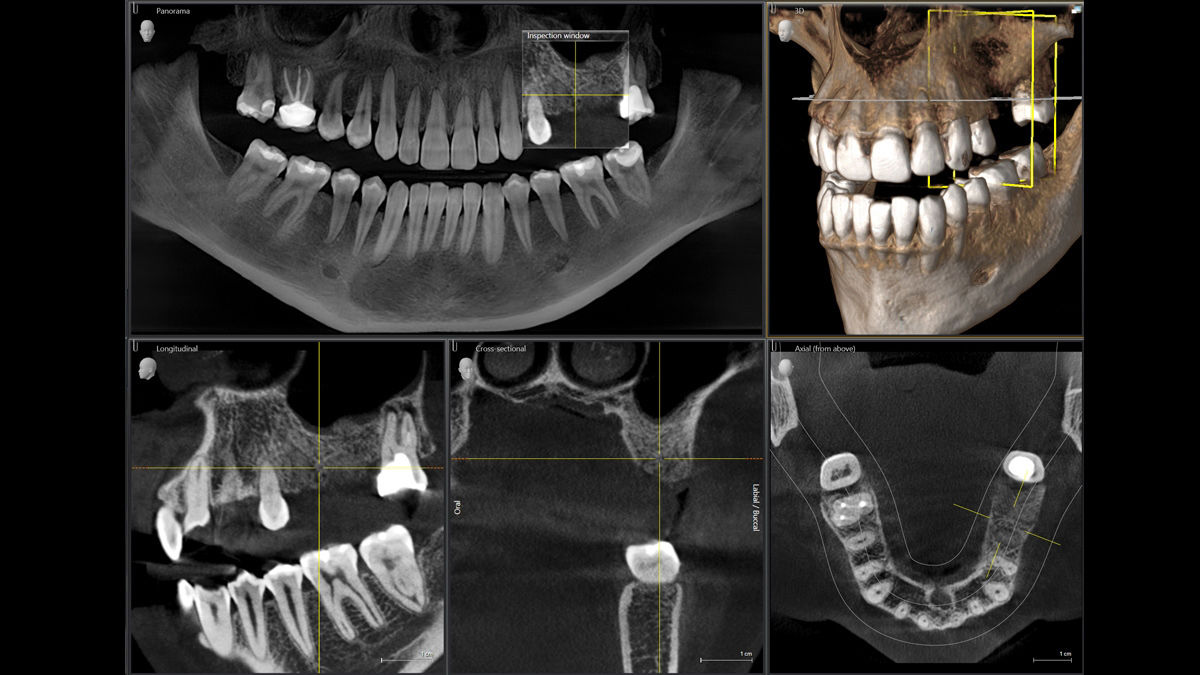

Software de reconstrucción MARS

Los objetos radiopacos, como los metales, causan interferencias en la captación de imagen. El software MARS reconoce automáticamente y reduce estos objetos, ayudando en el diagnóstico sin necesidad de realizar una segunda tomografía.